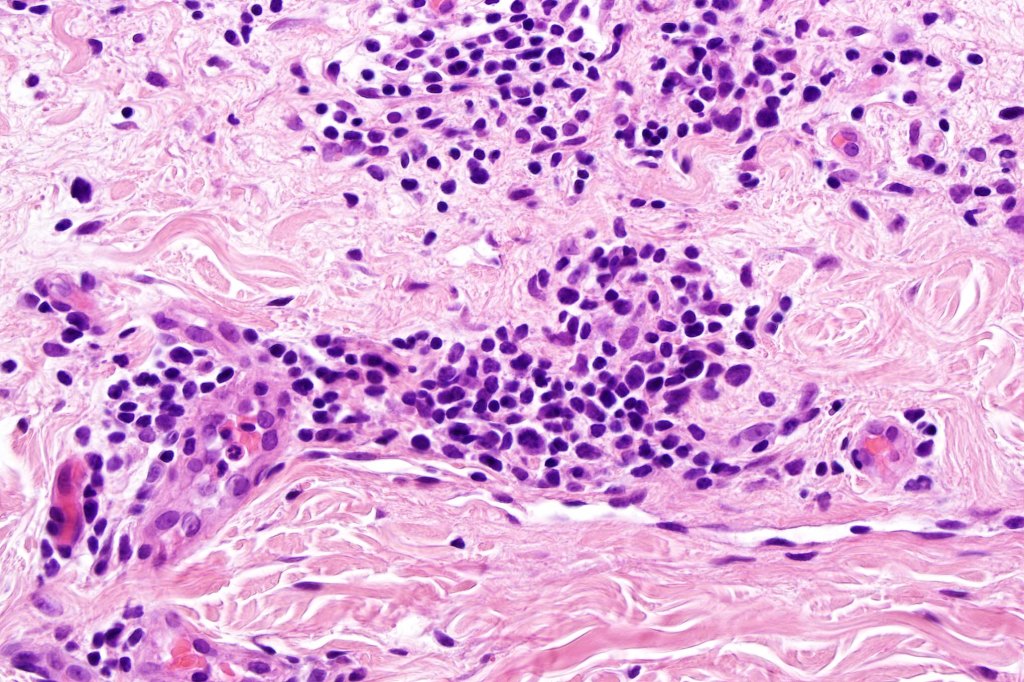

Histological features

•Variable histological features ranging from a non-specific superficial perivascular or band-like dermal infiltrate with minimal or no epidermotropism through to mycosis fungoides-like histology; can mimic atopic dermatitis

•Sézary cells are CD45RO, CLA, CD158 & CD4+

.Loss of CD7 (40% or more) & CD26 (30% or more)

•Variable loss of CD2, CD3 & CD5